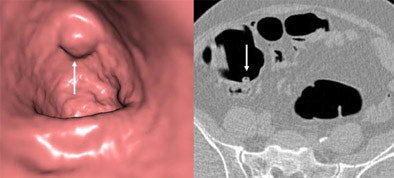

![]() |

| In a 57-year-old-male referred for VC screening, what appears to be a polyp on the 3D view (left) is correctly interpreted as a lipoma on 2D view (right). Colonoscopy confirmed a 27-mm lipoma. Images courtesy of Dr. Michael Macari. |